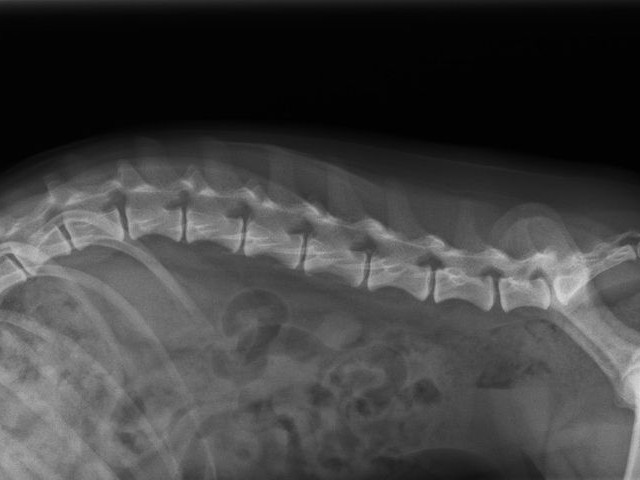

動物用CTを用いた検査が可能です。経験豊かな獣医師が患者様の状況に合わせて最善の検査・治療をご提案いたします。また、軟部組織外科など難度の高い手術症例にも対応しています。